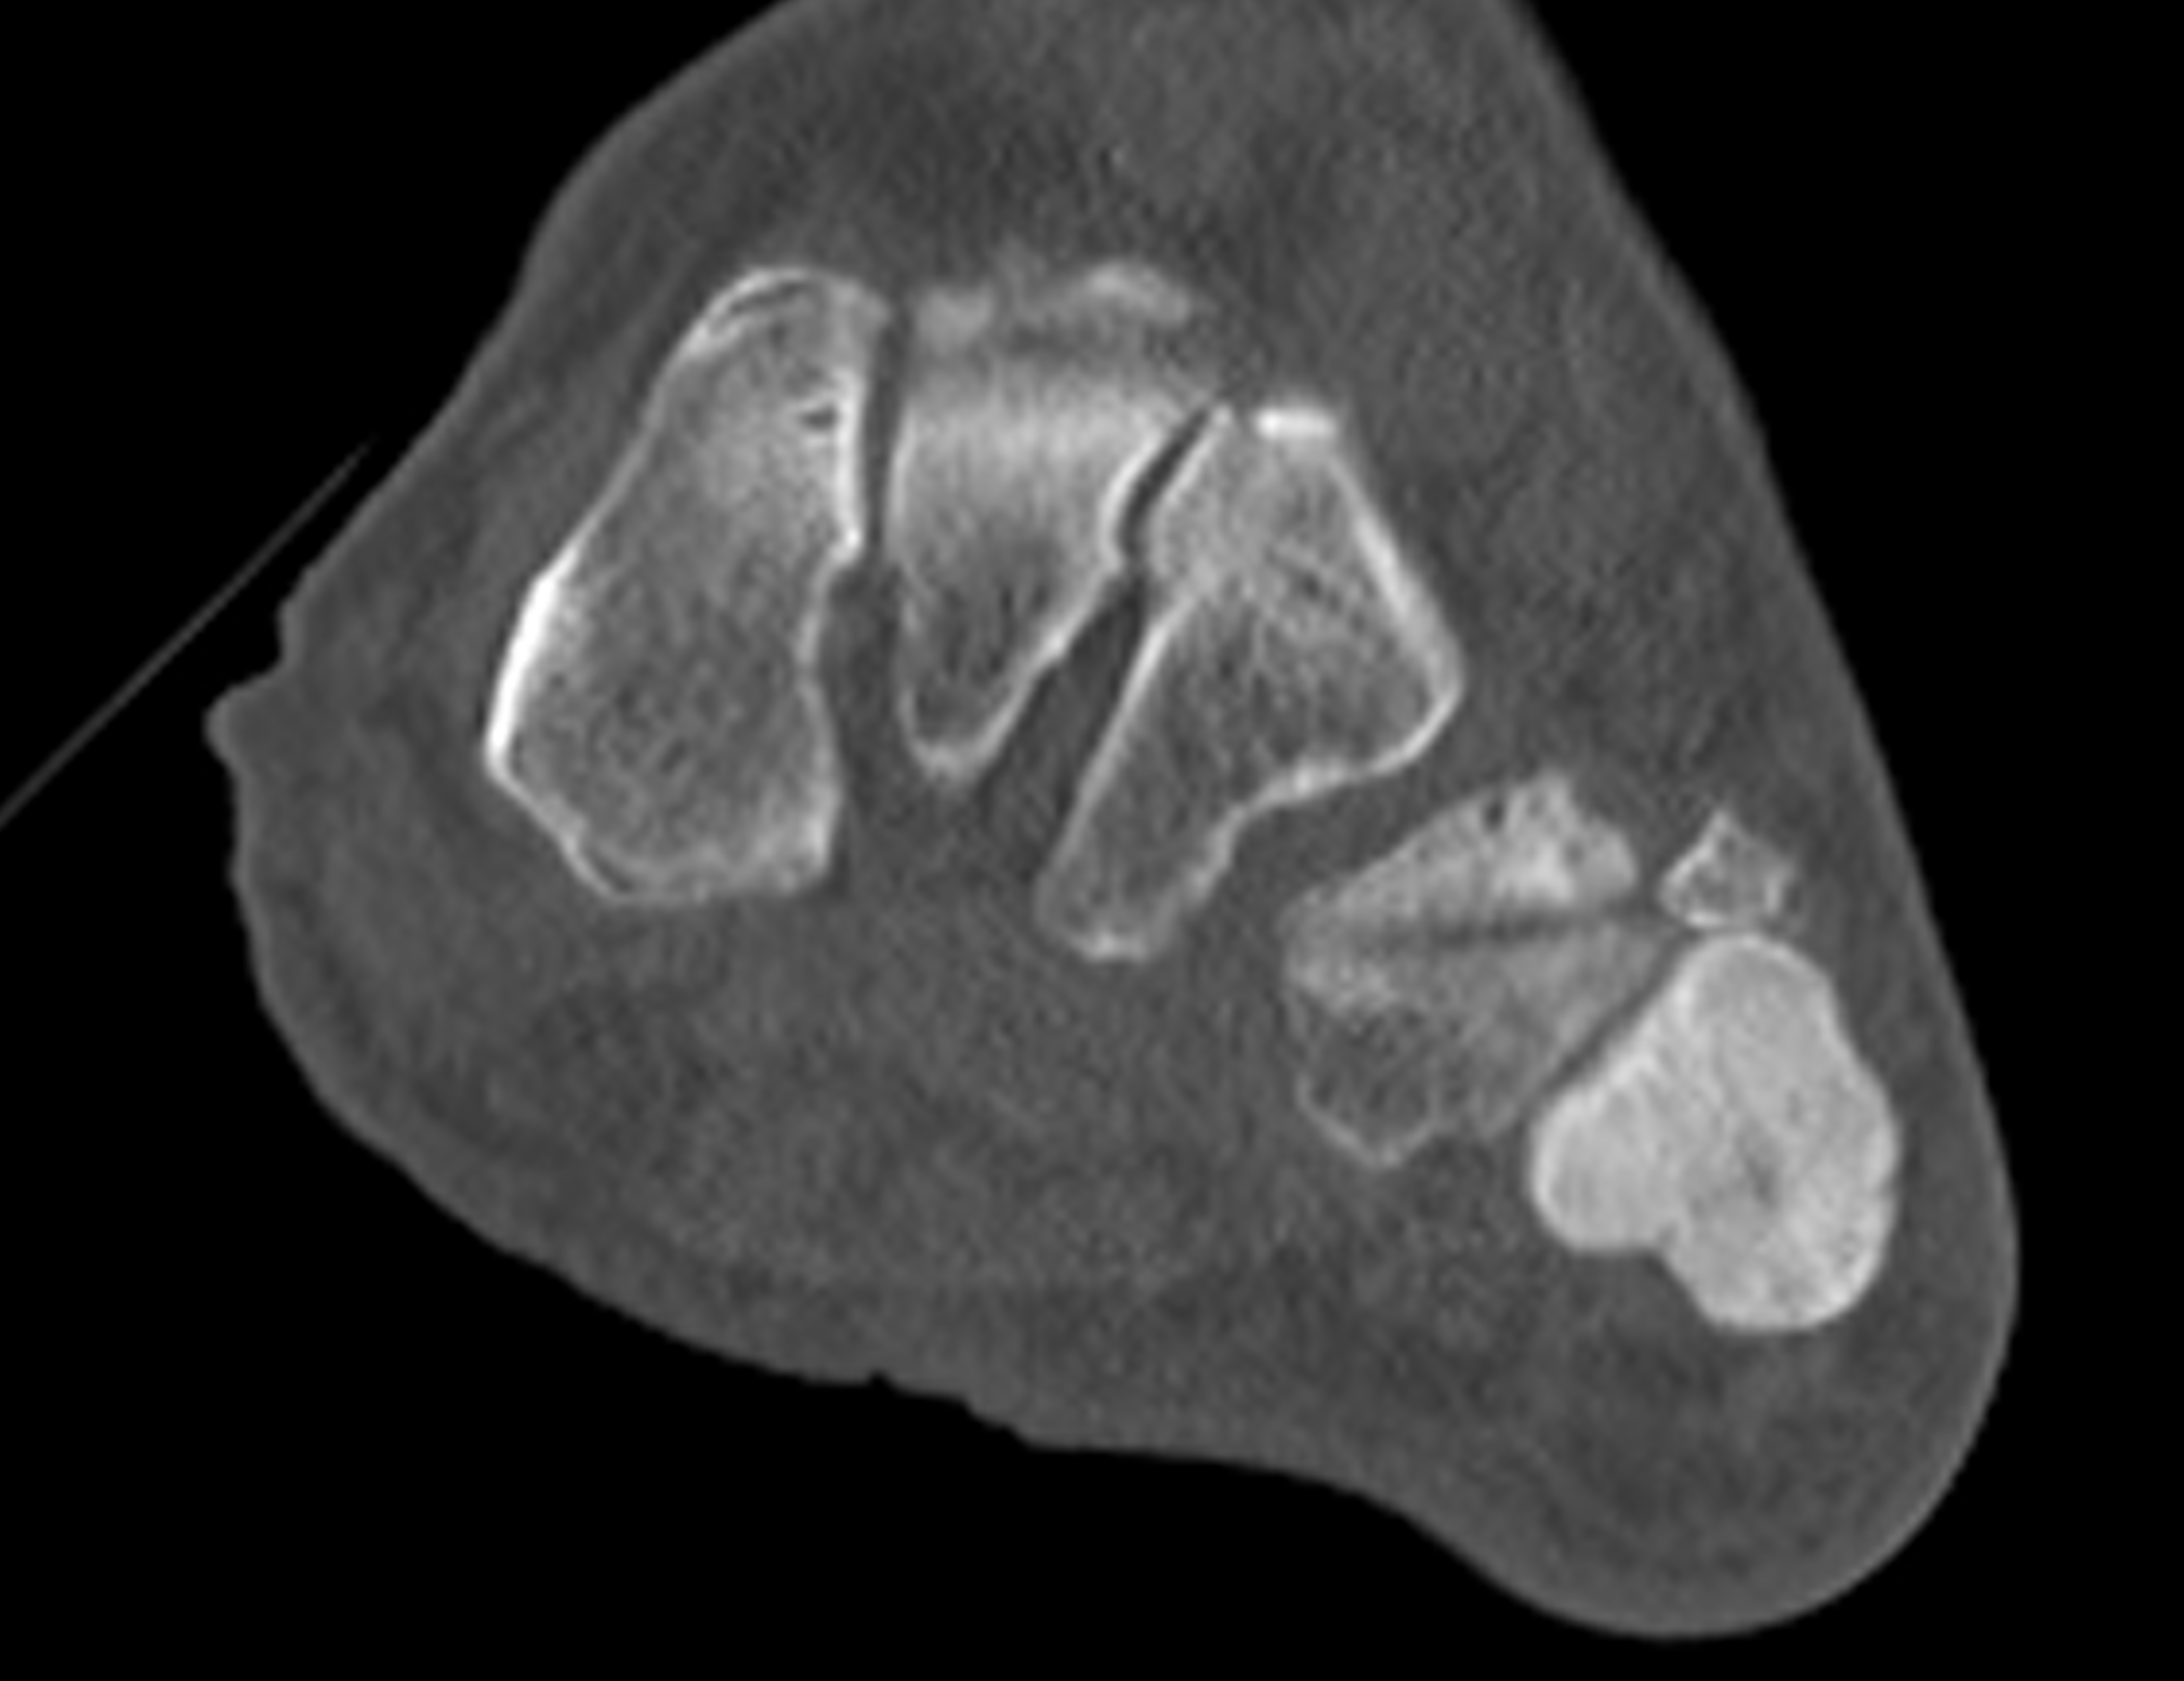

Figure 2: (2A) Sagittal T1-weighted image shows severe thickening of the distal femoral cortex (yellow arrow) and thickening and coarsening of the trabeculae in the femoral condyles (red arrow). Note the high signal intensity fatty marrow in both regions. (2B) Axial fat-suppressed, fluid sensitive sequence through the distal femoral shaft shows severe thickening of the bone cortex, with small round and tubular high-signal intensity foci within the cortex (arrow), likely representing cysts and dilated vascular spaces. (2C) Axial fat-suppressed, fluid sensitive sequence through the femoral epicondyles shows heterogeneous marrow (asterisks), with areas of suppressed marrow fat, mildly increased marrow signal intensity, and small cyst-like lesions. (2D) AP radiograph shows typical findings of mixed phase Paget disease in the distal femur including cortical thickening, course trabeculae, and bone enlargement. Secondary medial compartment predominant osteoarthritis has developed, likely contributing to symptoms.

Figure 9: Sclerotic phase Paget disease of the fifth metatarsal, MRI pattern 3. (9A) Sagittal T1-weighted image shows nearly uniform hypointense marrow in the fifth metatarsal, with small islands of preserved marrow fat (arrows), which helps exclude a malignant process. (9B) Sagittal fat-suppressed T2-weighted image shows mildly increased signal intensity throughout the marrow (asterisk). (9C) Dorsoplantar radiograph demonstrates sclerosis throughout the fifth metatarsal, due to cortical and trabecular thickening. Note the bone enlargement and bowing. (9D) Short-axis CT image shows nearly uniform sclerosis throughout the fifth metatarsal.